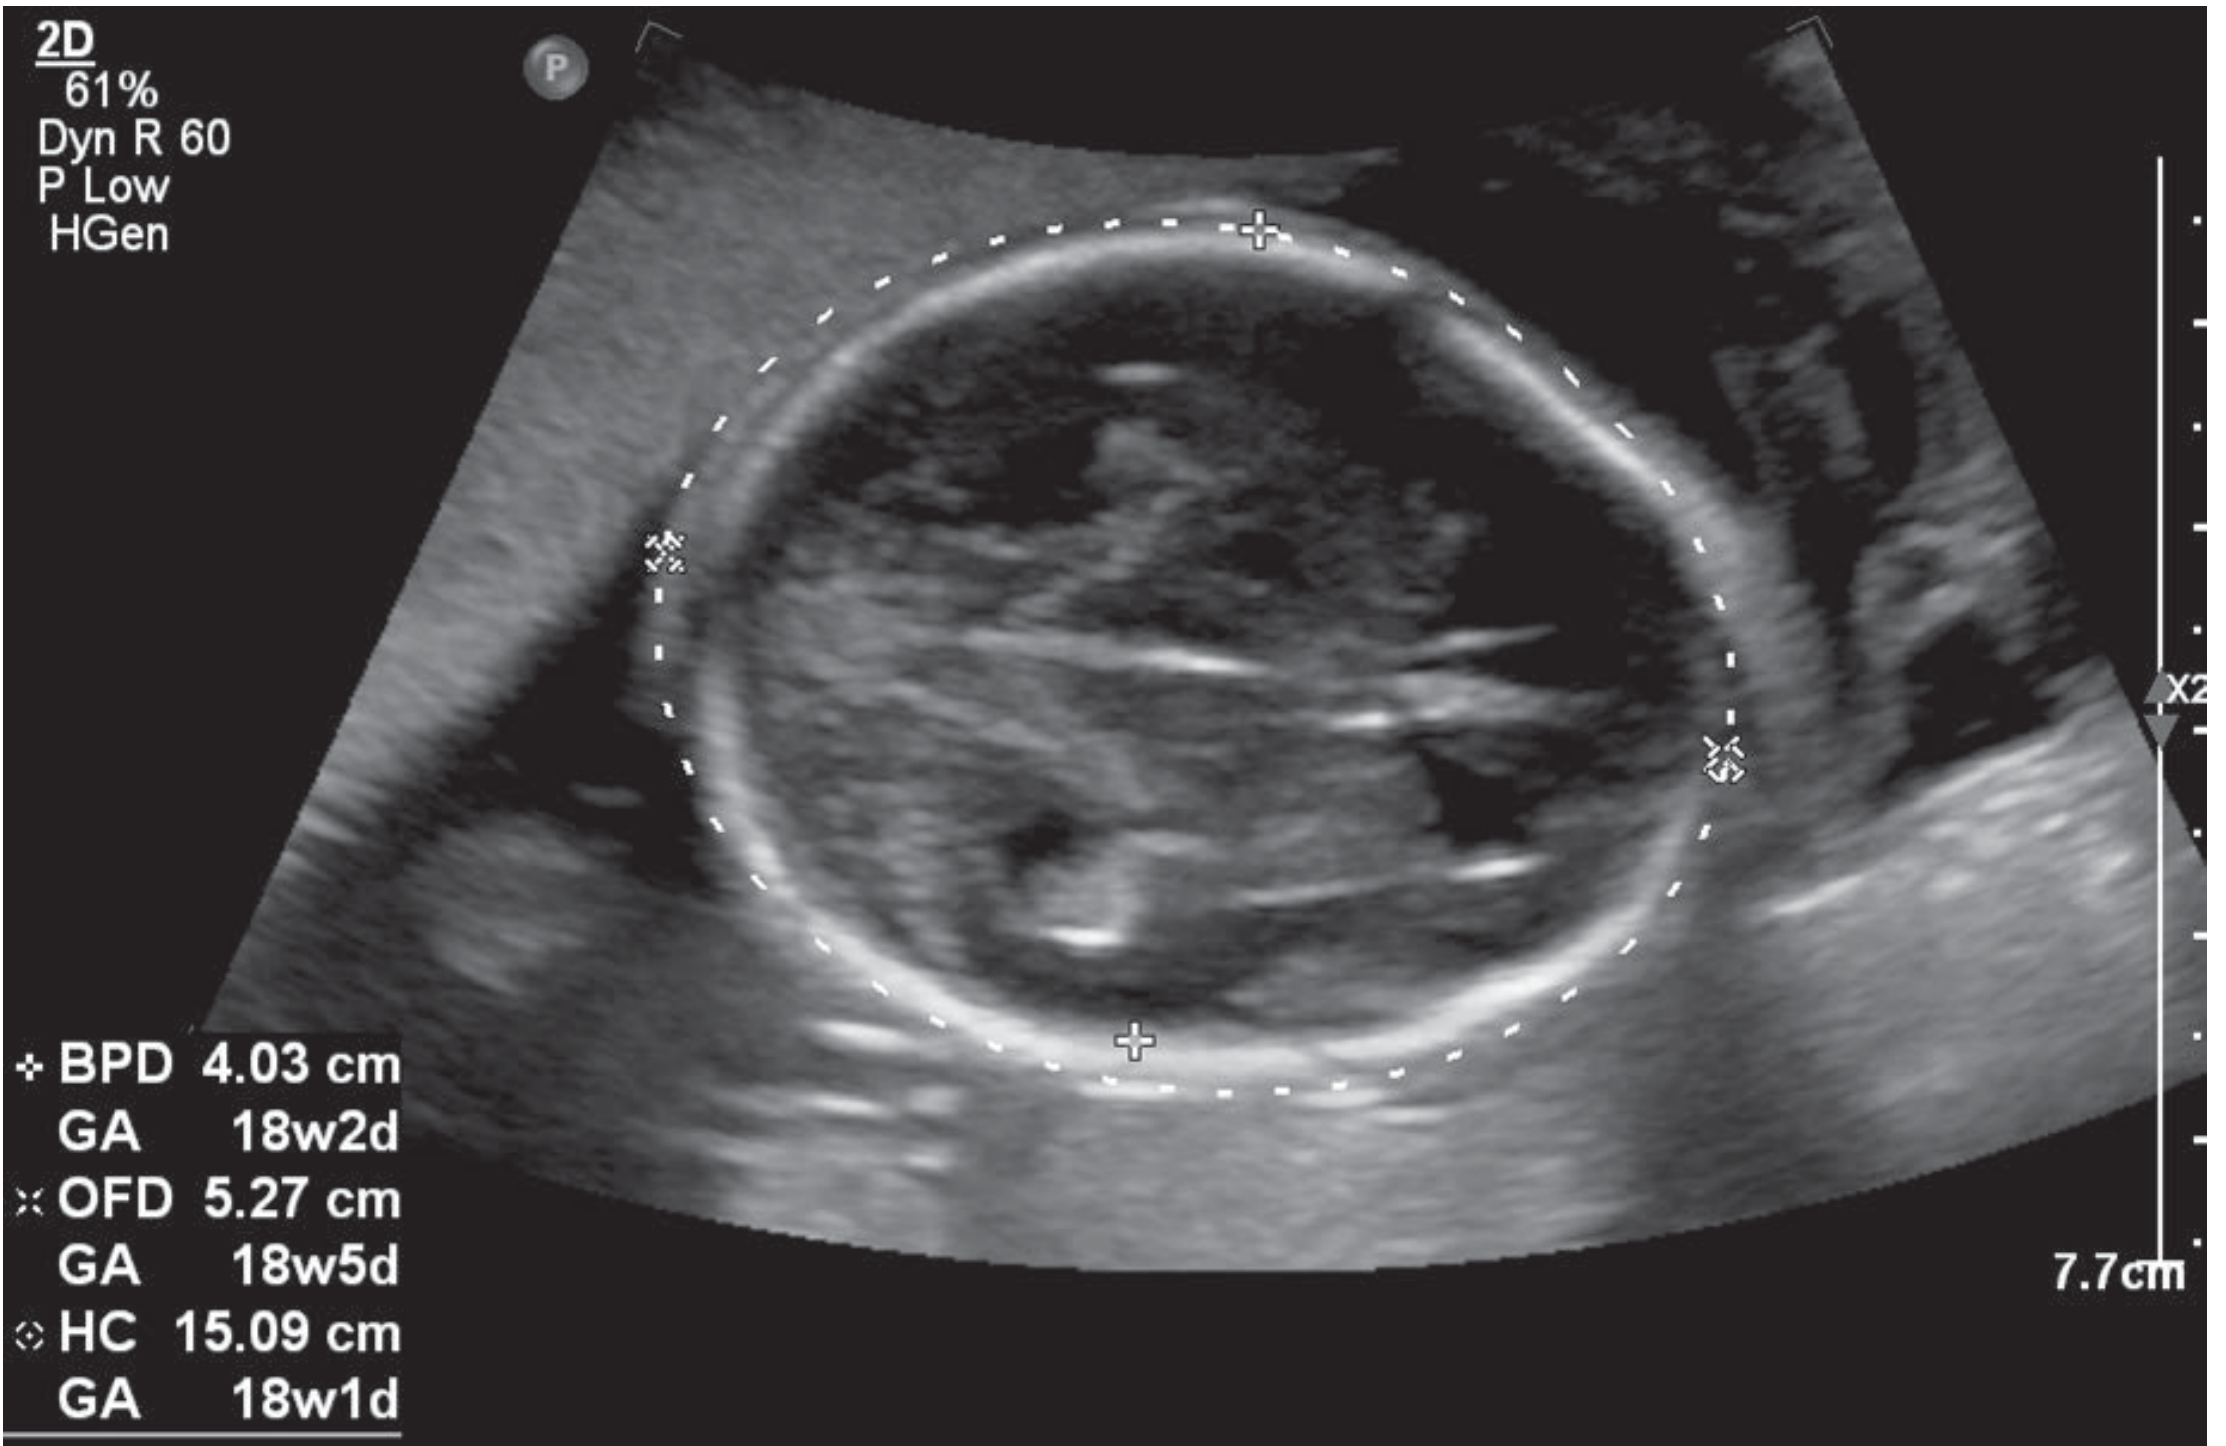

Head circumference (HC) and BPD measurement

Figure: Head circumference (HC) and BPD measurement

Fetal Biometry (Standard Measurements)

MeasurementAbbreviationPlane

Biparietal diameterBPDAxial transthalamic plane

Head circumferenceHCSame axial plane

Abdominal circumferenceACAxial plane at stomach/umbilical vein

Femur lengthFLLong axis of femur

These four measurements are used to calculate Estimated Fetal Weight (EFW) and gestational age.